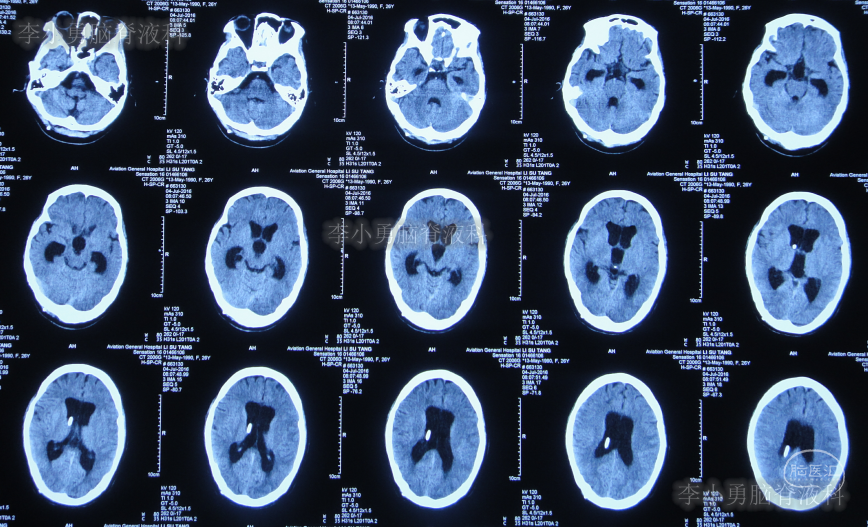

第三家医院第3次门诊图-1

图-1:2016年3月18日头颅CT

第三家医院第2次建议回家观察1周后即2016年4月3日,症状仍未缓解反而越来越重,于是,就诊于第四家位于上海市徐汇区的某三甲医院,查头颅CT后(图-2)“认为无明显异常”,怀疑癫痫。

图-2:2016年4月3日头颅CT

家属为进一步明确病因即2016年4月4日,第2次就诊并住入第二家的上海市静安区的某三甲医院,复查头颅影像后(图-3、图-4),给予按癫痫进行治疗。

图-3:2016年4月4日头颅CT